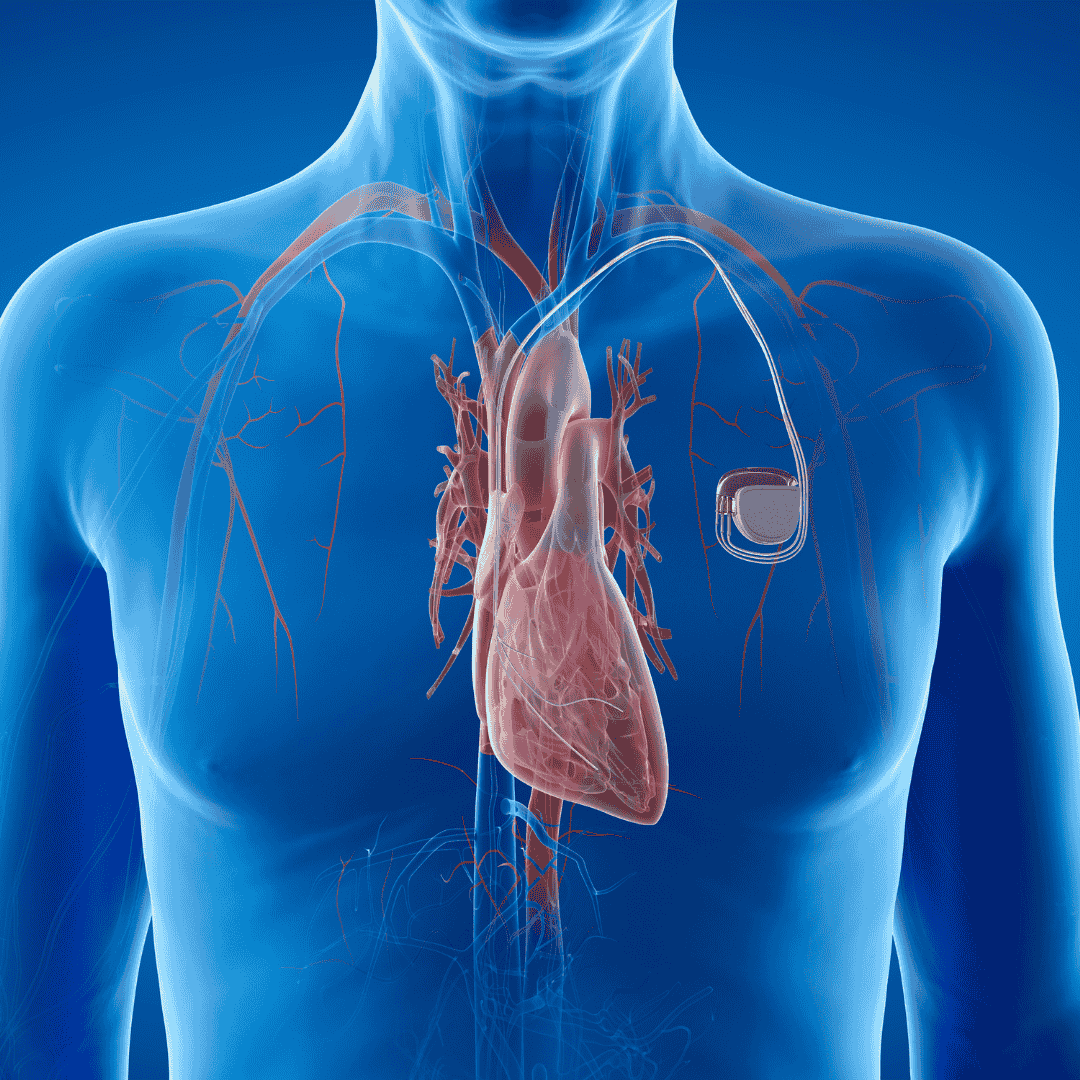

What Is Pacemaker Implantation?

Pacemaker implantation is a life-saving procedure designed to regulate the heartbeat in patients with arrhythmias or irregular heartbeats. This small device helps control heart rate, ensuring the heart beats at a proper rhythm.